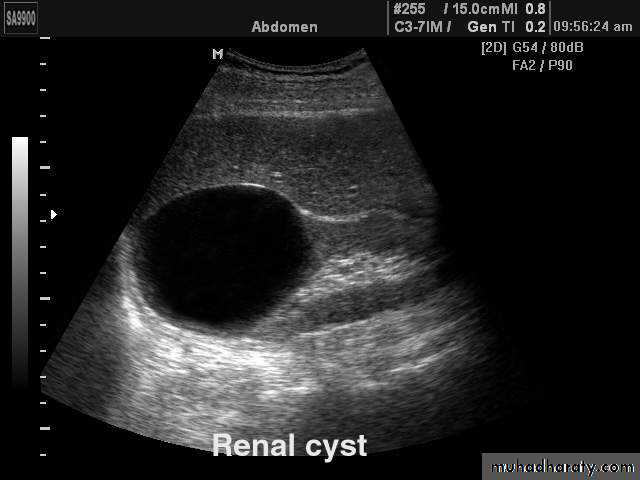

Simple cysts

Very common.

Filled with clear fluid(i.e anechoic).

Show obvious echoes from the front and back walls and posterior acoustic enhancement.

Most are spherical in shape.

Imperceptible walls

Solitary or multiple ,unilocular (simple)or have septations (not a simple cyst)

If contain low level echoes in dependent portion complicated by Hhg or infection.

No further investigations are needed.